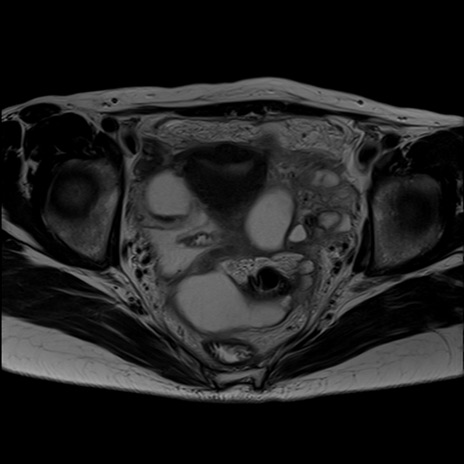

症例39 T2WI(横断像)

【症例】40歳代女性

【主訴】上下腹部痛

【現病歴】2日目から下腹部痛あり。夜間は痛みで眠れなかった。昨日より上腹部痛と下痢が出現。臥位で痛みは軽快したため、休んでいた。本日になって臥位でも立位でも痛みが強くなってきたため救急要請。

【既往歴】子宮内膜症

【身体所見】部:平坦・軟、左上下腹部に圧痛あり、反跳痛あり。

【データ】WBC 21800、CRP 26.78

MRI(4日後)